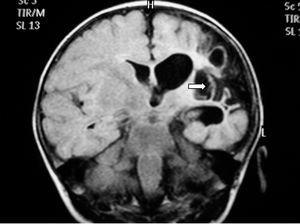

Ante los hallazgos clínicos, a los 3 días de vida se realiza resonancia magnética (RM) cerebral, apreciándose un extenso infarto agudo dependiente de la arteria cerebral media derecha (fig. 1). El EEG y la ecografía cerebral realizadas a los 5 días, mostraron, respectivamente, presencia de ondas agudas frontales derechas ocasionales y un aumento de ecogenicidad en la región parietal, temporal derecha y tálamo derecho. Se completó el estudio con una ecografía Doppler cerebral y una angio-RM (fig. 2) que objetivaron ausencia de flujo en arteria cerebral media derecha confirmando el diagnóstico de infarto cerebral.

Figura 1.RM axial con técnicas de difusión (DWMRI). Ausencia de señal en el lóbulo parietal derecho.